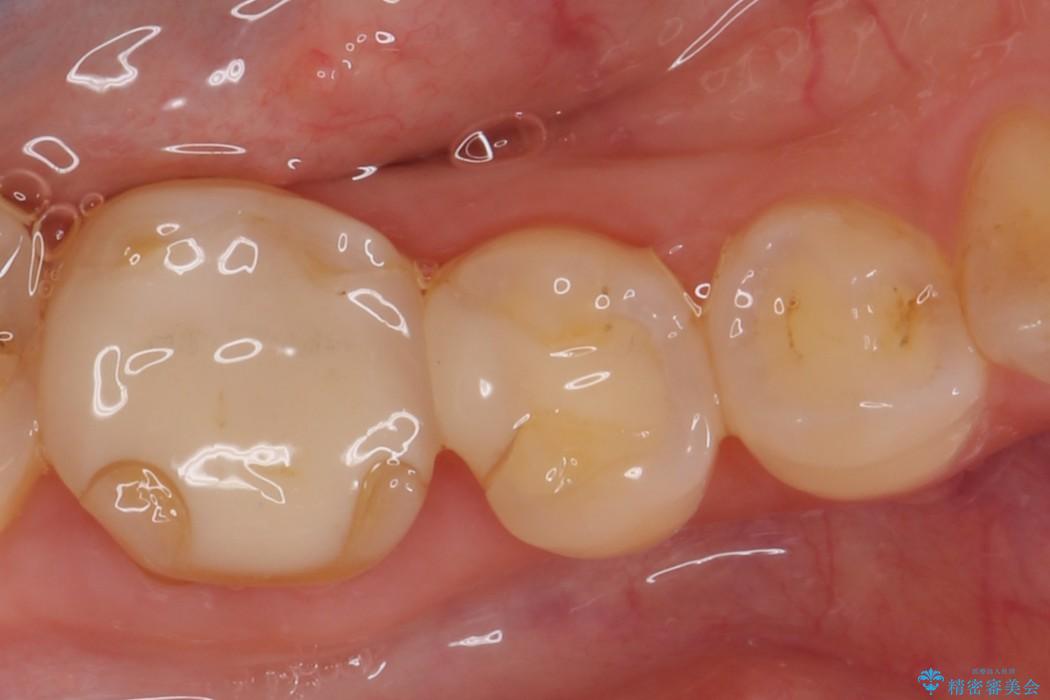

ぱっと見ただけでは特に問題ないように見えますが、レントゲンをよく確認すると詰め物と歯の間に隙間がはっきりと確認ができます。

適合不良であるインレーを放置するリスクを患者様へ説明してご納得いただいた上で、オールセラミックインレーで治療を行うこととしました。